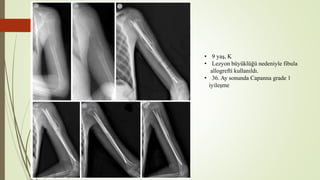

• 9 yaş, K

• Lezyon büyüklüğü nedeniyle fibula

allogrefti kullanıldı.

• 36. Ay sonunda Capanna grade 1

iyileşme